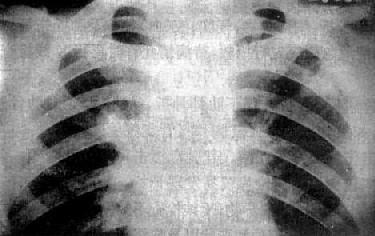

X线表现是病变多发生在两肺中、下野的内、中带。支气管及周围间质的炎变表现为肺纹理增多、增粗和模糊。小叶性渗出与实变则表现为沿肺纺理分布的斑片状模糊致密影,密度不均(图3-1-18)。密集的病变可融合成较大的片状。病变广泛可累及多个肺叶。小儿患者常见肺门影增大、模糊并常伴有局限性肺气肿。

图3-1-18 支气管肺炎

肺门影增大,肺纹理增强、模糊,中、下肺

野可见沿肺纹理分布的斑片状模糊致密影